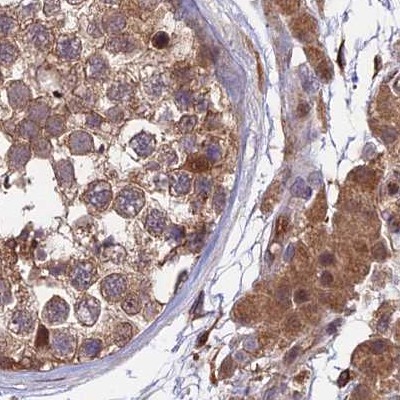

Immunohistochemical staining of human colon, kidney, testis and urinary bladder using Anti-MKKS antibody HPA041071 (A) shows similar protein distribution across tissues to independent antibody HPA044233 (B).